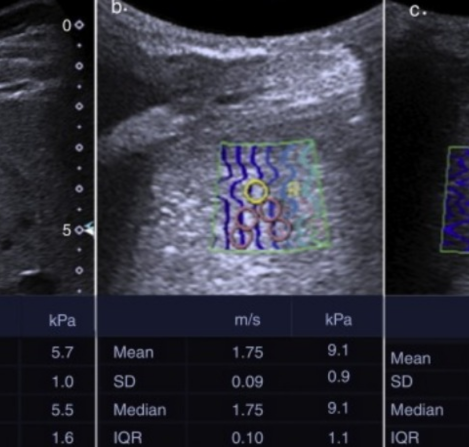

Servicios Valadéz Radiólogos